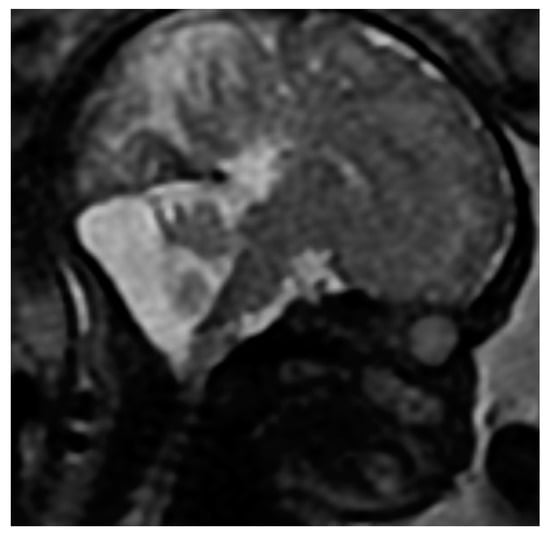

3.2.3. Defects of the Posterior Fossa

Defects of the Cerebellum

Dandy-Walker Syndrome

Arnold-Chiari Syndrome

3.2.5. Other Irregularities

Abnormalities Related to Peripheral Nervous System Defects

Meningo-Spinal Hernia

Arachnoid Cyst